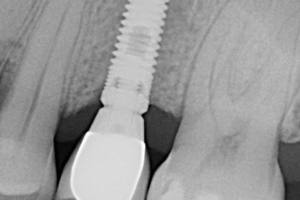

· Imagen 11, leer más...

La cirugía implantológica consiste en la inserción de un implante roscado en el hueso disponible mediante el fresado gradual de un lecho. Tras la colocación del mismo se procede a la rehabilitación protésica correspondiente atornillada a dichos pilares. Dentro de la implantología no hay que someterse únicamente a la inserción y rehabilitación de los implantes dentales, sino que también hay un abanico de tratamientos para mantener y preservar la integridad de los mismos así como de tratar las complicaciones que puedan aparecer.